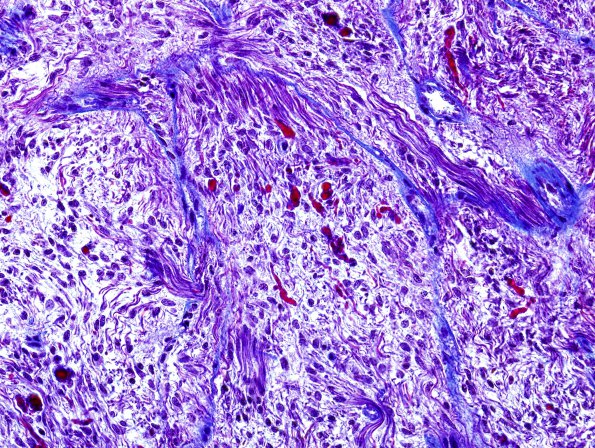

24E Astrocytoma, pilocytic (Case 24) Trichrome 4

Trichrome stains Rosenthal fibers a striking red color.